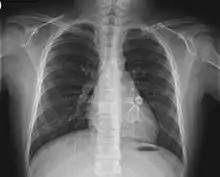

- Electrocardiogram may show evidence of ventricular dysfunction or, occasionally, arrhythmia due to myocarditis.

- Echocardiogram may show subtle coronary artery changes or, later, true aneurysms.

- Angiography was historically used to detect coronary artery aneurysms, and remains the gold standard for their detection, but is rarely used today unless coronary artery aneurysms have already been detected by echocardiography.